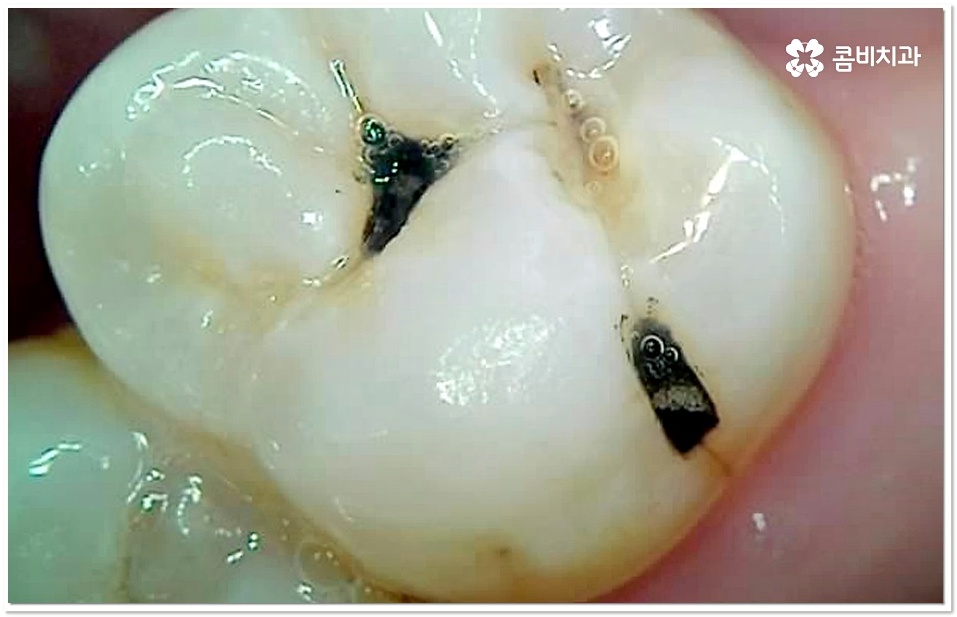

충치 초기에는 손상이 크지 않고 대부분 겉면인 법랑질에 국한되는 경우가 많아 해당 부위를 깨끗하게 삭제한 후 레진으로 직접 때우는 방법을 통해 보다 빠르고 간편한 수복을 할 수 있어요. 그러나 충치가 더 진행되면 손상 부위가 넓고 깊어지기 때문에 레진 처치는 적합하지 않으므로 인레이나 온레이와 같이 보철물을 만들어 끼워주는 방법을 이용하고 있는데요. 특히 어금니는 씹는 힘을 많이 받는 치아이기 때문에 보통 인레이와 같이 내구성이 더 높은 어금니 충치치료 방법을 많이 쓰고 있어요.

충치 초기라고 하더라도 만약 저작면이 아닌 인접면 충치가 생긴 경우에는 상황에 따라 레진 치료가 아닌 인레이 어금니 충치치료 방법을 쓸 수 있는데요. 이때 치아 옆면을 재건해야 하는 경우처럼 까다로운 케이스에 있어서는 더욱 세심한 주의력과 숙련된 노하우가 필요할 거예요.